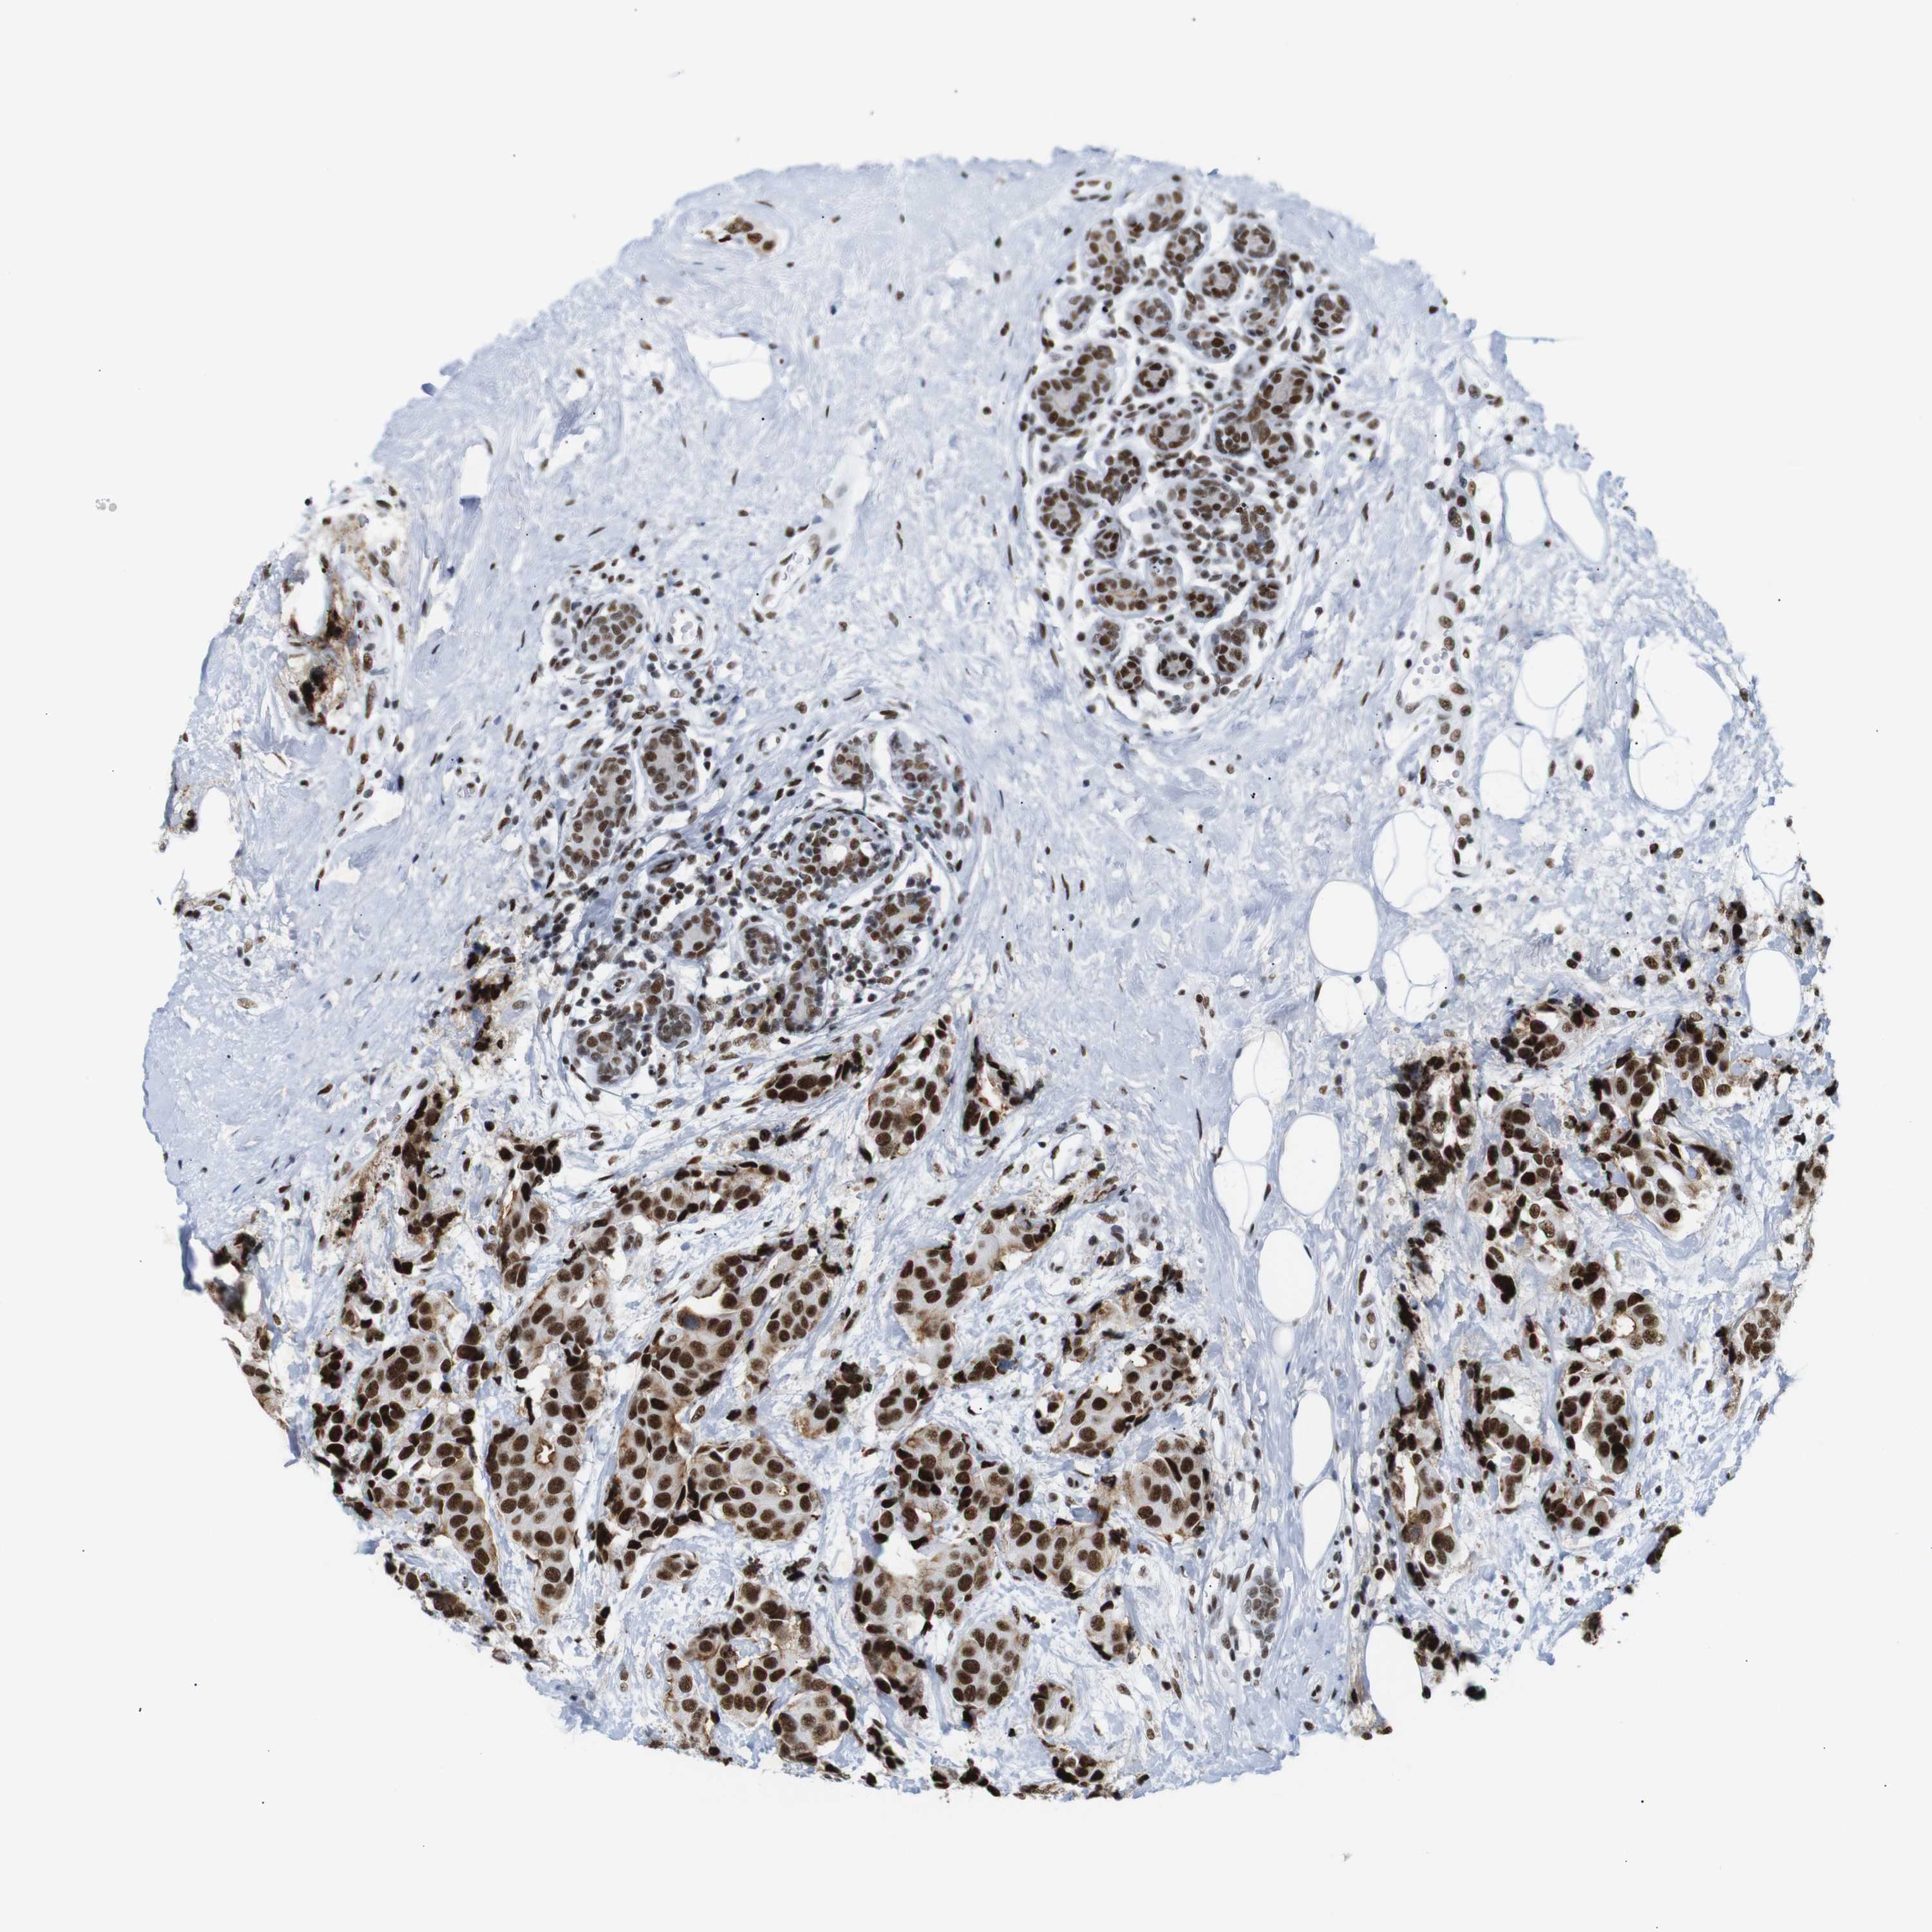

BRCA TCGA BRCA VALIDATION PROTEIN EXPRESSION